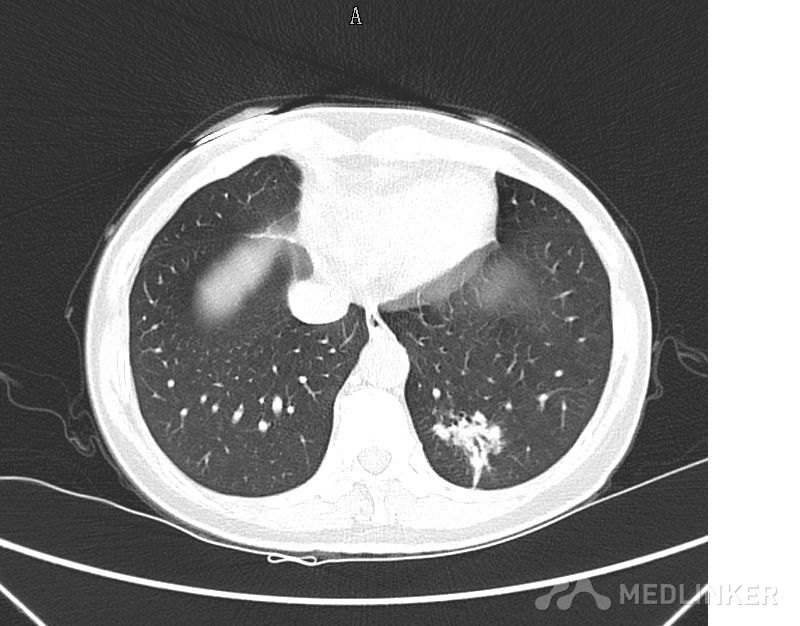

大家看看这个肺部的占位可能是什么?

肺部肿物

以CT图片为准,中年男性,反复咳嗽半个月入院,有低热,痰不多,无咯血,饮食睡眠正常。